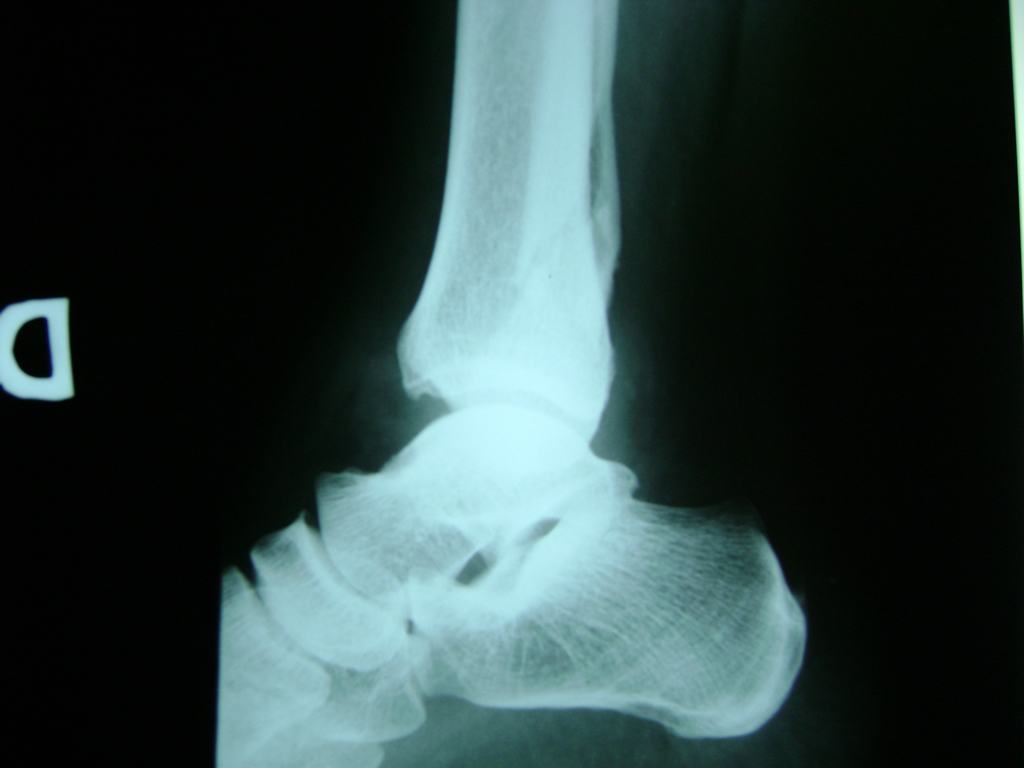

Algunas fracturas de tobillo pueden requerir cirugía si:

- Los extremos de los huesos están desalineados entre sí (desplazados).

- La fractura se extiende hasta la articulación del tobillo (fractura intra-articular).

- Los tendones o ligamentos (tejidos que sujetan los músculos y los huesos entre sí) están rotos.

- El médico cree que sus huesos probablemente no sanen apropiadamente sin cirugía.

- El médico considera que la cirugía puede permitirle una recuperación más rápida y confiable.

- En los niños, la fractura involucra la parte del hueso del tobillo donde el hueso está creciendo.